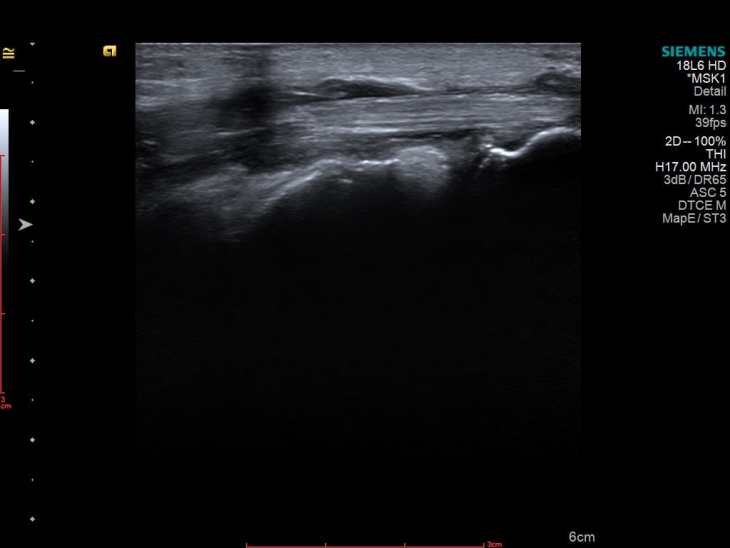

УЗД 3-го пальця продемонструвало не просто запалення, а його розгорнуту, системну картину, а саме виражений випіт у всіх суглобах пальця, потовщені м’які тканини та ознаки ентезиту сухожилків згиначів. Такий комплекс змін вже не вписувався в ізольований подагричний напад.

Картина доповнилася після обстеження гомілковостопного суглоба, бо було виявлено активний теносиновіт.

І що важливо — при всій цій запальній активності УЗД не показало жодної типової для подагри ознаки: ні подвійного контуру, ні тофусів.